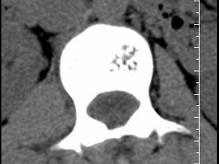

问题 根据所提供的图像,选择最可能的诊断 ( )

选项 A、退行性变 B、骨质疏松 C、多发性骨转移 D、骨血管瘤 E、骨结核

答案 D